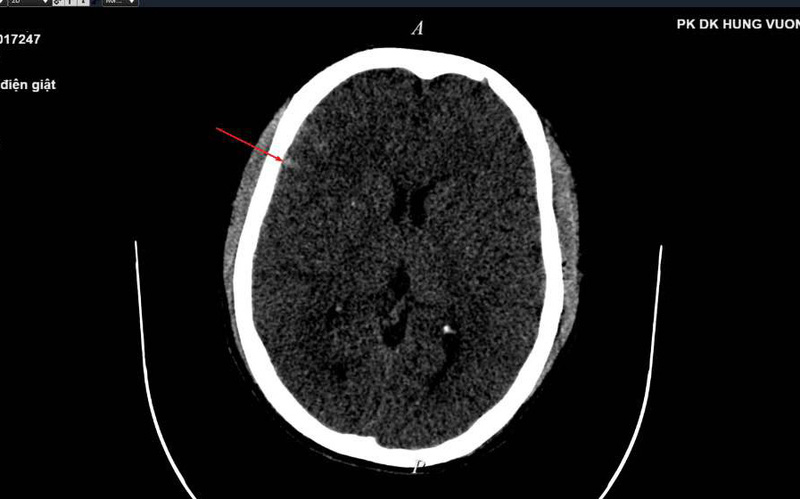

Bệnh nhân nhanh chóng được sơ cứu vết thương, xử trí cấp cứu giảm đau, tiêm phòng SAT, đưa bệnh nhân đi thực hiện chụp cắt lớp vi tính, chụp X-quang, siêu âm và thực hiện các cận lâm sàng khác.

Kết quả chụp phát hiện tụ máu ngoài màng cứng vùng dương trái kèm xuất huyết dưới nhện rải rác vài rãnh cuộn não thùy thái dương và đỉnh phải, vỡ xương thái dương và xương đỉnh trái…